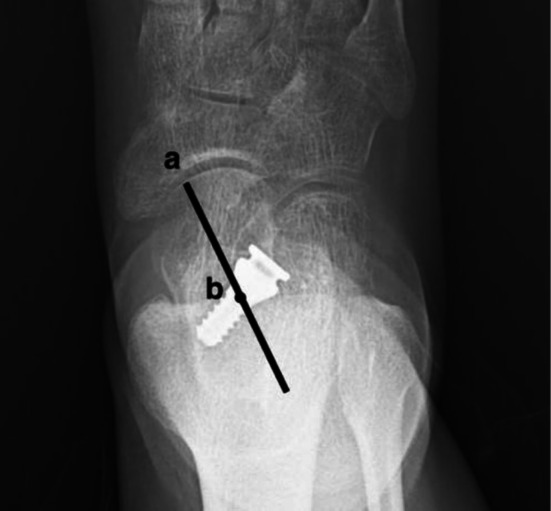

Purpose: Although subtalar arthroereisis (SA) with HyProCure is increasingly utilized for progressive collapsing foot deformity (PCFD), evidence regarding risk factors for complications remains limited. This study aimed to analyze the influencing factors and correlations of sinus tarsi pain and implant removal in PCFD patients after SA utilizing the HyProCure device.

Methods: A retrospective study was conducted involving 223 patients (236 ft) diagnosed with PCFD who underwent SA from June 2015 to June 2023. General data and surgical data such as patient gender, age, body mass index (BMI), surgical side, any adjunctive surgeries, length of stay, HyProCure size, and HyProCure depth were collected. Complications were also recorded. Statistical analysis included normality assessment, inter-group comparisons (t-tests for normal quantitative data, Mann-Whitney U for non-normal data, and chi-square for categorical variables). Spearman correlation analyzed factors associated with sinus tarsi pain and implant removal. Binary logistic regression identified risk factors.